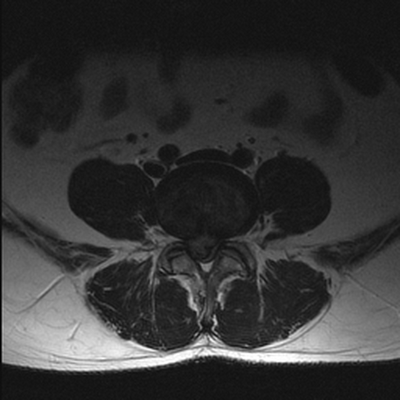

МРТ поясничного отдела позвоночника. Остеоартрит и остеоартроз дугоотростчатых суставов. Аксиальная Т2-взвешенная МРТ.